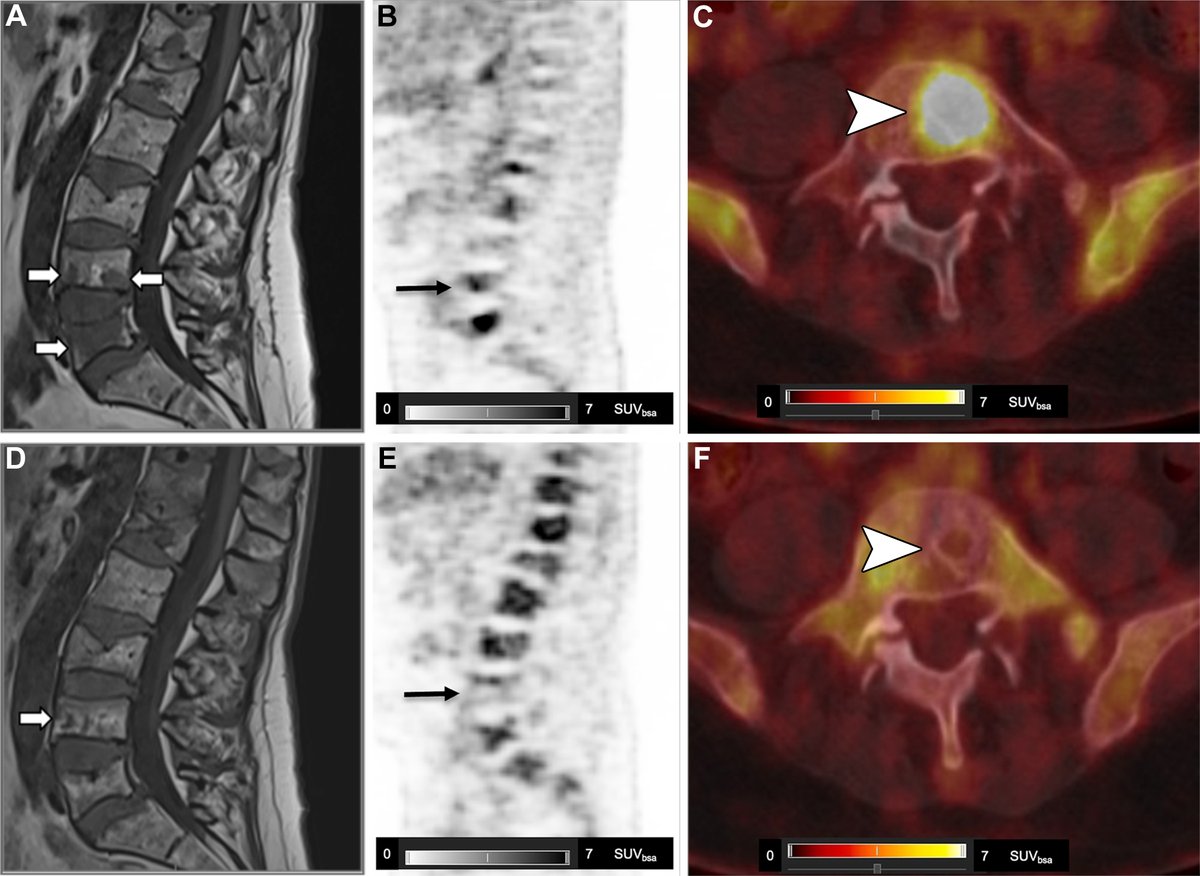

WB-DW MRI or FDG PET/CT for myeloma response? This review breaks down strengths, pitfalls, and standardized criteria (MY-RADS & Deauville). Learn how to integrate both for accurate posttreatment assessment and improved confidence. bit.ly/4viX1Wi